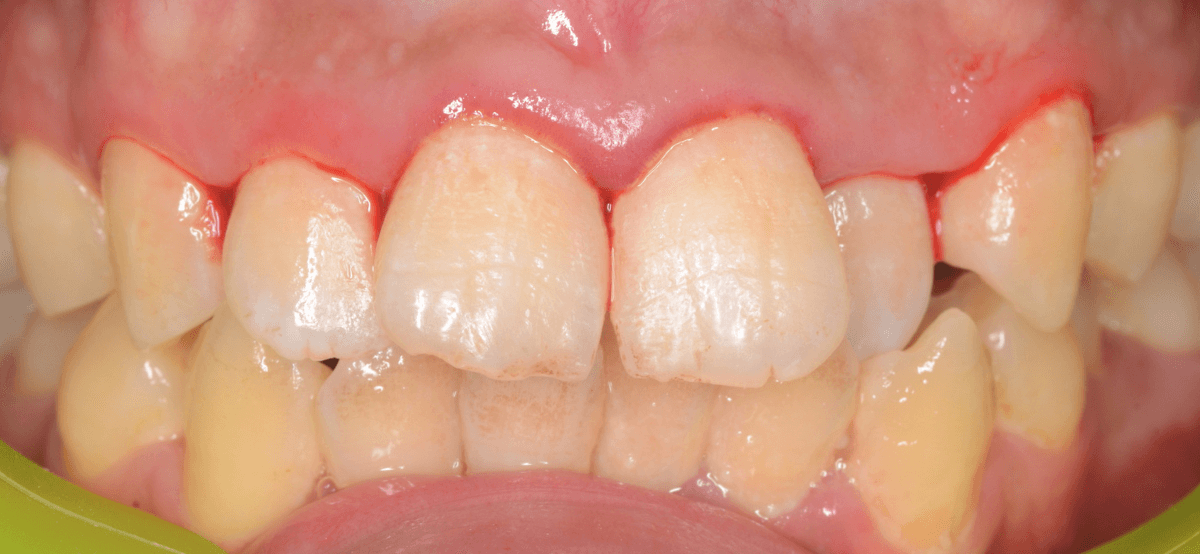

歯石除去後、約1週間です。

歯肉がひきしまってきたのがわかるでしょうか。

治療前との比較です。

比べると、違いがわかると思います。

まだ若い患者さんで本格的な歯周病に進行する前ですので、歯ブラシの徹底によって、もっと歯肉が改善されるのも期待できます。